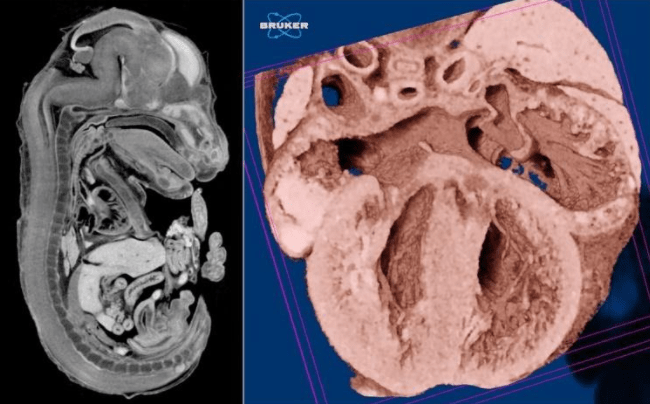

Embryology and Developmental Biology

Embryology and developmental biology studies require high resolution 3D imaging of embryos, such as of the mouse. However without contrast agent staining, very little soft tissue detail is visible. Here a soft tissue contrast agent, phosphotungstic acid (PTA), is used to stain mouse embryos for micro-CT imaging. The SkyScan micro-CTs achieve the high contrast necessary to distinguish anatomical structures, in the short acquisition scan required to conduct large studies.